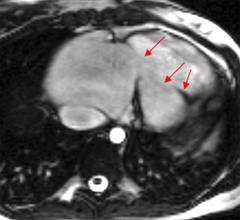

– Il importe de bien connaitre la séméiologie propre aux séquences dont on dispose pour apprécier les jets de perte de signal liés aux flux rapides en séquence ciné.

– Les séquences de cartographie de flux ‘through-plane’ et ‘in-plane’ permettent une bonne approche hémodynamique des valvulopathies.